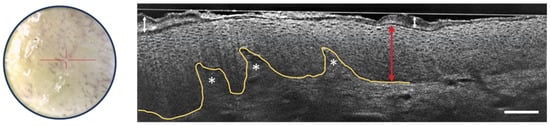

LC-OCT provides valuable criteria for the detection of basal cell carcinoma, particularly focusing on the visualization of dermal lobules (see Figure 7) [32]. Among these criteria, three distinct components within a lobule are identified as the most important for BCC recognition:

Figure 7.

Dermoscopic image (left) and vertical sectional LC-OCT image (right) of a superficial basal cell carcinoma (BCC) (a), a nodular BCC (b) and an infiltrative BCC (c). The core of the lobule is characterized by a millefeuille pattern (blue dotted lines) delimited by its clefting (orange arrow) and bright rim (green arrow). The yellow line represents the partially drawn DEJ. The red horizontal line superimposed on the dermoscopic image delineates the location of the vertical sectional LC-OCT image. Scale bars: 100 µm.

- Grey core with millefeuille pattern: This component appears as a laminated structure oriented along the horizontal plane, resembling the layers of the French pastry “millefeuille”. It represents the dense cellularity within the basaloid tumor island and includes basaloid and immune cells.

- Middle dark rim (clefting): Immediately surrounding the grey core of the lobule, the middle dark rim is referred to as “clefting” and likely corresponds to the peritumoral mucin deposition [33].

- Outer bright rim: This rim results from the compression and alteration of collagen fibers in the stroma due to the presence and interaction of the tumor island, creating a mass effect.

This detailed characterization of the core of the BCC lobule is possible due to the high-resolution, high-penetration, and vertical/3D visualization capabilities of LC-OCT. The simultaneous presence of the inner lamination, middle clefting, and outer bright rim aids in the differentiation of BCCs from other cutaneous lesions displaying dermal lobules. Moreover, LC-OCT allows for the subtyping of BCCs based on lobule shape and position [34]. For instance, hemispheric lobules connected to the epidermis are associated with superficial BCC (Figure 7a), while macrolobules separated from the epidermis are characteristic of nodular BCC (Figure 7b), and branched lobules in the dermis are indicative of infiltrative BCC (Figure 7c). These criteria are useful in real-life clinical situations for correct BCC diagnosis and subtyping without the need for biopsy, enabling appropriate therapeutic decisions to be taken immediately. The integration of LC-OCT in dermatological practice empowers practitioners with improved diagnostic confidence and efficiency in managing BCC cases. The LC-OCT ability to provide additional information, complementing dermoscopy, makes it a valuable non-invasive tool for accurate BCC detection and subtyping [35]. A recent three-year study has shown the potentially important role of LC-OCT in the non-invasive diagnosis of non-melanocytic skin tumors, particularly BCC, avoiding unnecessary biopsies with increased sensitivity, much higher specificity, and better accuracy than clinical assessment with dermoscopy alone [36].